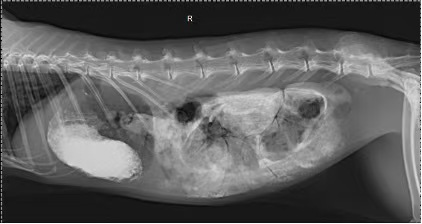

To confirm this, we decided to conduct a contrast radiograph of the stomach. The results showed a high-density image in the stomach, which led us to believe that there might be an obstruction. Based on the radiographic findings, we decided to perform an exploratory laparotomy to identify the object in the stomach.